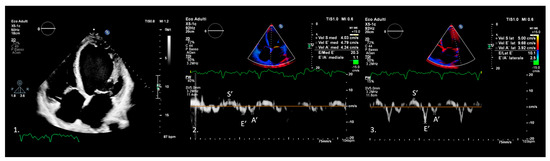

3. Tissue Doppler Imaging Characteristics